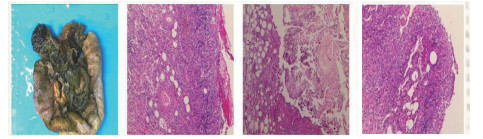

1 资料与方法患者男,30岁,因“腹胀、腹痛6 d,高热1 d”于2017年12月11日由广州南沙区中心医院转诊收入中山大学孙逸仙纪念医院全科医学科。患者本次起病前无明确病因或明显诱因。患者以左上腹轻微胀痛起病,进行性加重。南沙区医院查血常规:白细胞14.27×109/L,血小板50×109/L,中性粒细胞比例74.5%,嗜酸粒细胞1.02×109/L,嗜酸粒细胞比例7.2%。全腹CT+CTA提示:门静脉左右主干及其小分支栓子形成。后在3 d内连续复查血常规,提示血小板进行性下降,由50×109/L相继降至35×109/L、18×109/L;(嗜酸粒细胞计数及比例未能提供),并出现高热(体温39.5℃),因病情危重,遂转诊本院。入院时患者精神疲乏、高热,腹部胀痛难忍,伴有咳嗽。查体:体温38.6℃,心率87次/min,血压102/76 mmHg,指尖血氧饱和度90%~91%。双肺呼吸音粗,双肺均可闻及小水泡音。腹部稍膨隆,叩诊鼓音,左上腹及脐周轻压痛,无反跳痛。听诊肠鸣音减弱,约1~2次/min。当天查血常规示白细胞11.85×109/L,血小板23×109/L,中性粒细胞比例58.1%,嗜酸粒细胞3.5×109/L,嗜酸粒细胞比例29.5%。凝血常规提示:PT 15.9S,PTA 51.1%,PT/R 1.39,Fbg 1.59 g/L,PTINR 1.39,APTT 35.2 s,D-二聚体114.36 mg/L FEU(参考值范围0~0.55 mg/L FEU)。胸部+全腹部CT+CTA示“门静脉主干及左、右支、肠系膜上静脉近端栓子形成;腹主动脉及左侧髂总动脉小附壁血栓;左肺上叶尖后段、左肺上叶下舌段、右肺中叶及双肺下叶炎症;乙状结肠两段节段性管壁增厚,建议排外占位性病变;腹水、盆腔积液,大网膜炎性病变可能性大”。每日复查血常规,发现血小板进行性下降,最低至15×109/L(参考值范围125~350×109/L),嗜酸粒细胞计数及比例进行性升高,分别达到8.07×109/L(参考值范围0.020~0.52×109/L)和51.1%(参考值范围0.4-8.0%)。每日复查凝血常规亦提示凝血指标不断恶化,纤维蛋白原最低降至0.63 g/L。在予禁食、“美平(美罗培南)”抗感染、输注纤维蛋白原及血小板、维护水电解质平衡及营养支持的积极治疗的同时,还积极完善了以下检查寻找病因:①血液系统方面:血浆鱼精蛋白副凝实验:阳性(+);凝血功能实验:PT 15.5S↑,PTA 47.8%↓,PT/R 1.35↑,PTINR 1.36↑,APTT 40.4 s↑,AT-Ⅲ 57.7%↓,F-VII 32.8%↓,F-Ⅷ 68.1%↓,F-X 68.0%↓,F-XII 24.0%↓;纤维蛋白降解产物:381.4 mg/L↑;血栓弹力-血小板图:R时间10.3 min↑;角度18.5度↓;最大血块强度13.2 mm↓;MA(ADP)值5.6 mm↓。骨髓病理学:嗜酸性粒细胞增多(43%),巨核细胞减少(7个)。慢淋/淋巴瘤表型分析:获取和分析细胞数5.0万;粒细胞区百分比82.6%;淋巴细胞区百分比9.4%;单核细胞区百分比2.0%;CD45dim细胞区百分比1.3%;有核红及细胞碎片区域百分比4.6%。ETV6/PDGFRB融合基因、FIP1L1/PDGFRA融合基因(—)。骨髓细胞学病理结果:符合嗜酸细胞增多症;②消化系统检查:大便细菌培养鉴定及药敏提示无志贺、沙门菌生长,有真菌生长;大便难辨梭菌毒素检测(—);粪便找寄生虫、找阿米巴、寄生虫七项均为(—);消化肿瘤系列提示CA-125 244.8 U/mL↑;腹腔穿刺术穿出“血性腹水”,腹水CA-125 1006.0 U/mL↑,腹水找癌细胞(—);复查腹部CT+CTA:乙状结肠两段节段性管壁增厚,建议进一步检查;排外占位性病变;遂行PET-CT:提示全身未见明确恶性征象。行电子结肠镜示:内镜诊断:(1)回肠末段炎症;(2)乙状结肠炎症;(3)内痔。钳取组织送病理,提示:标本①(回肠末端)黏膜组织呈慢性炎,伴糜烂,一些嗜酸性粒细胞浸润(约35个/HPF);②(乙状结肠)黏膜组织呈慢性炎,伴糜烂,个别嗜酸性粒细胞浸润(约4个/HPF)。③风湿免疫系统方面:免疫八项、风湿四项:C反应蛋134.0 mg/L,余未见异常;总IgE 170 IU/mL↑;抗ENA抗体、狼疮两项、血管炎两项、免疫球蛋白G4、抗心磷脂抗体三项均为阴性;④其他感染病原学检查:乙肝、肝炎系列、性病三项、痰找抗酸杆菌、T-spot实验、流行性出血热、登革热抗体、登革热病毒NS1抗原、外斐氏试验、肥达氏试验、痰结核培养、骨髓培养、血液细菌、血液厌氧菌培养均为阴性。经过上述检查,初步考虑“特发性嗜酸性细胞增多症”,于12.15开始予“甲泼尼松龙40 mg静滴, 1次/d”及“低分子肝素0.6 ml皮下注射, 1次/d”抗炎抗凝治疗。患者病情及检验指标有所好转,热退、腹胀减轻,血常规提示血小板升至49 ×109/L,嗜酸粒细胞计数和比例均下降至正常,凝血常规提示D-二聚体降至47.90 mg/L FEU。但12-22患者自行进食多量米饭后突发腹胀痛较前加重,急查血常规提示白细胞升至21×109/L,血小板再次下降至15×109/L,D-二聚体升至97.28 mg/L FEU,全腹CTA提示“门静脉主干及左、右支、肠系膜上静脉近端新发栓子形成”,遂于当日转至ICU予“尿激酶20万U+肝素钠1250 U”溶栓治疗后予“低分子肝素0.6 ml皮下注射, 1次/12 h”序贯抗凝治疗。后患者病情渐渐稳定,至2018-1-18患者在“甲泼尼松龙12 mg口服, 1次/d”及“立伐沙班20 mg口服, 1次/d”的维持治疗下,血小板、嗜酸粒细胞计数及纤维蛋白原均回复正常,D-二聚体下降至3.52 mg/L FEU。但遗憾的是,此时患者再次进食大量米饭,约1 h后突发腹痛、气促,急行胸片+腹平片提示:“双侧膈下游离气体,考虑胃肠道穿孔可能;双下肺少许炎症,少量胸腔积液;腹部多量积气伴肠腔扩张”。遂即送手术室行全麻下“腹腔镜探查+坏死空肠切除+大网膜切除+肠系膜上动脉探查+空回肠双腔造口术”,术后病理提示标本①(大网膜)脂肪组织,部分坏死,合并慢性炎,伴一些中性粒细胞浸润,较多泡沫样组织增生,未见明确血栓,未见恶性改变。②(部分空肠)肠壁组织,部分肠壁全层坏死,合并慢性炎,肉芽组织增生,未见明确血栓,未见恶性改变。免疫组织化学:CD38浆细胞(+)、IgG(+)、IgG4(﹣)。术后继续予“立伐沙班10 mg/d”和“甲泼尼松龙8 mg/d”口服治疗,并于2018.2.4停用“甲泼尼松龙”。2.28复查全腹CTA,仍可见“脾静脉新发血栓,门静脉及肠系膜上静脉血栓较前好转”。3.20行空回肠双腔造瘘管泛影葡胺造影术提示“双腔造瘘管通畅,右中下腹小肠蠕动尚可,结肠各段及直肠通畅,未见对比剂外漏征象”。但患者合并了严重的短肠综合征,致严重低钾低钠血症和继发的代谢性脑病,病情再度转危。继续纠正电解质紊乱、补充营养,最终病情好转后于4.11行“造瘘口回纳修补术”。随访半年,患者仍口服“立伐沙班10 mg/d”抗凝治疗,复查血常规、凝血常规等各项指标均正常,但营养状况较差。

| 图 3 腹腔镜探查+坏死空肠切除+大网膜切除+肠系膜上动脉探查+空回肠双腔造口术后病理(2018-1-19):可见部分肠壁全层坏死,合并慢性炎症,肉芽组织增生 |